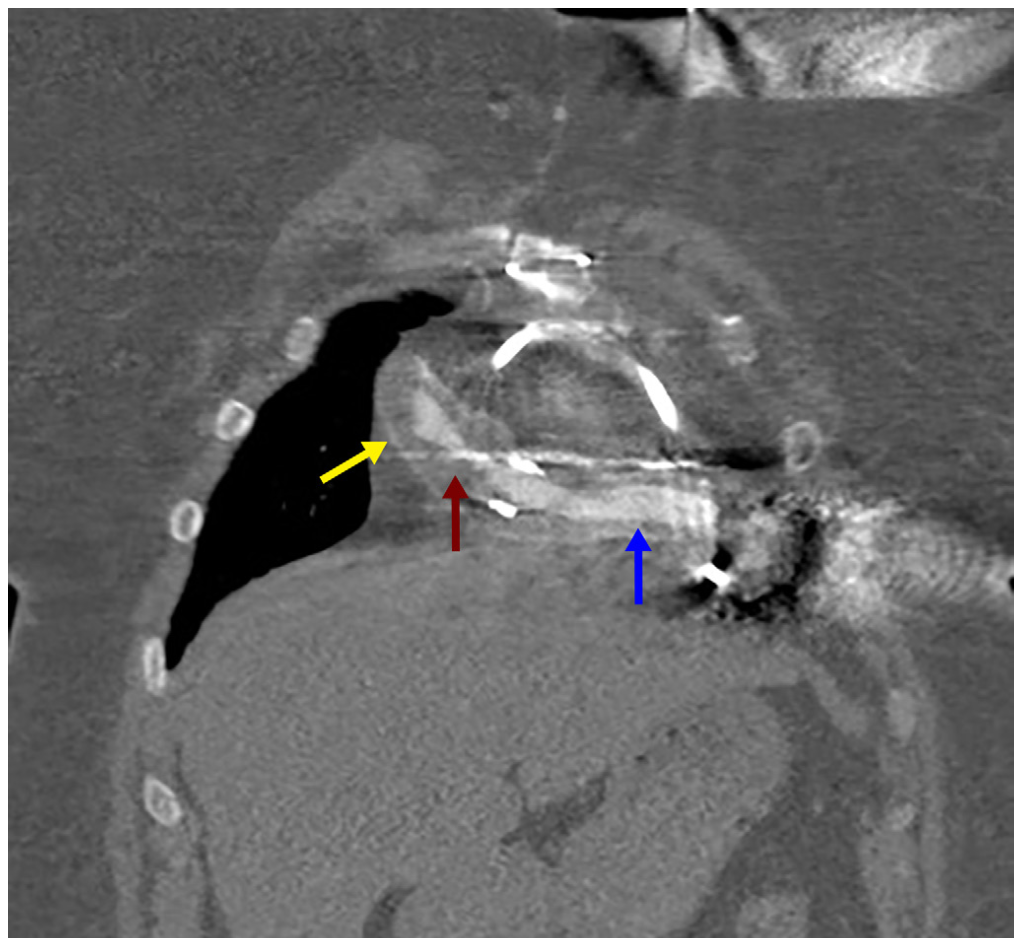

Given her body mass index of 42 kg/m2 and anterior take-off of the graft, left brachial access provided easier engagement of the outflow graft with the use of a 6-Fr multipurpose-B1 guide catheter. Intravascular ultrasound (IVUS) confirmed extrinsic compression in the mid portion of the graft, narrowing it to 4 mm. The stenosis was treated with a 10- x 60-mm balloon followed by an 11- x 79-mm VBX balloon-expandable covered stent (Medtronic). Repeat IVUS confirmed good apposition of the stent and resolution of the stenosis (Figure 4 and Figure 5; Video Series).